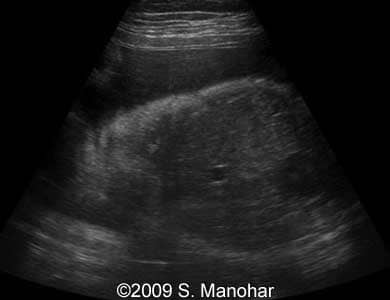

Images 3, 4: The image 3 shows a sagittal scan of the fetal head with protruding tongue (left part of the image). The right part of the image 3 and the image 4 represent a coronal scan at the level of the fetal lips, which are turned outward (so called "eclabion"). Hyperechoic incisor teeth can be seen in the opened mouth.

3

7